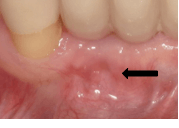

Floss threaders come in two basic styles: plastic loops and prethreaded. Plastic loops are sturdy but may be too large for tight spaces—lower lingual retainers placed too close to the tissues or impenetrable implant bridge come to mind. On the other hand, prethreaded versions are fragile and break easily, rendering them useless and requiring a new piece. Cotton pliers can assist in guiding the threaders and giving extra reach. If you trust the patient, those who have trouble threading may benefit from a pair of pliers for home use.Chronic dental infections, trauma, and dental implant complications can lead to dental fistulas.3 Fistulas are tracks of infection that originate from a source and extend to the surrounding soft tissue, dissecting through the path of least resistance.3 The head will look like a pimple and its presence should immediately trigger further investigation.